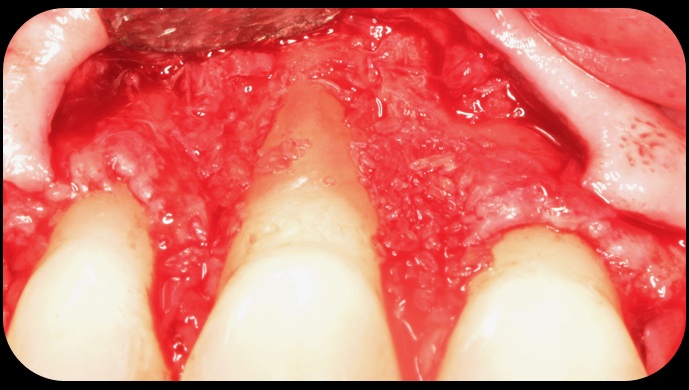

Then, too, are opportunities to prepare the site for regeneration by coupling therapies, applying an enamel matrix derivative, along with traditional bone grafts of demineralized freeze-dried bone allograft; potentially, gains in attachment with minimal probing depth and retained papilla may avoid the need for an implant (Figure 2 through Figure 7).

Demineralized freeze-dried bone allograft.

Fig. 5